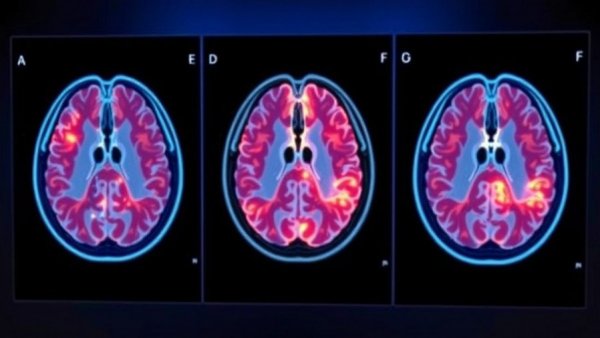

The significance of this walk extends far beyond a single event; it shines a spotlight on the harsh realities of Alzheimer’s, which affects over 7 million Americans. Not only do these individuals grapple with cognitive decline, but their families undergo profound emotional and practical challenges. In Florida alone, more than 580,000 individuals face this disease, while about 870,000 caregivers selflessly offer their support without compensation. The day of the walk provides both a space for remembrance and a catalyst for change.